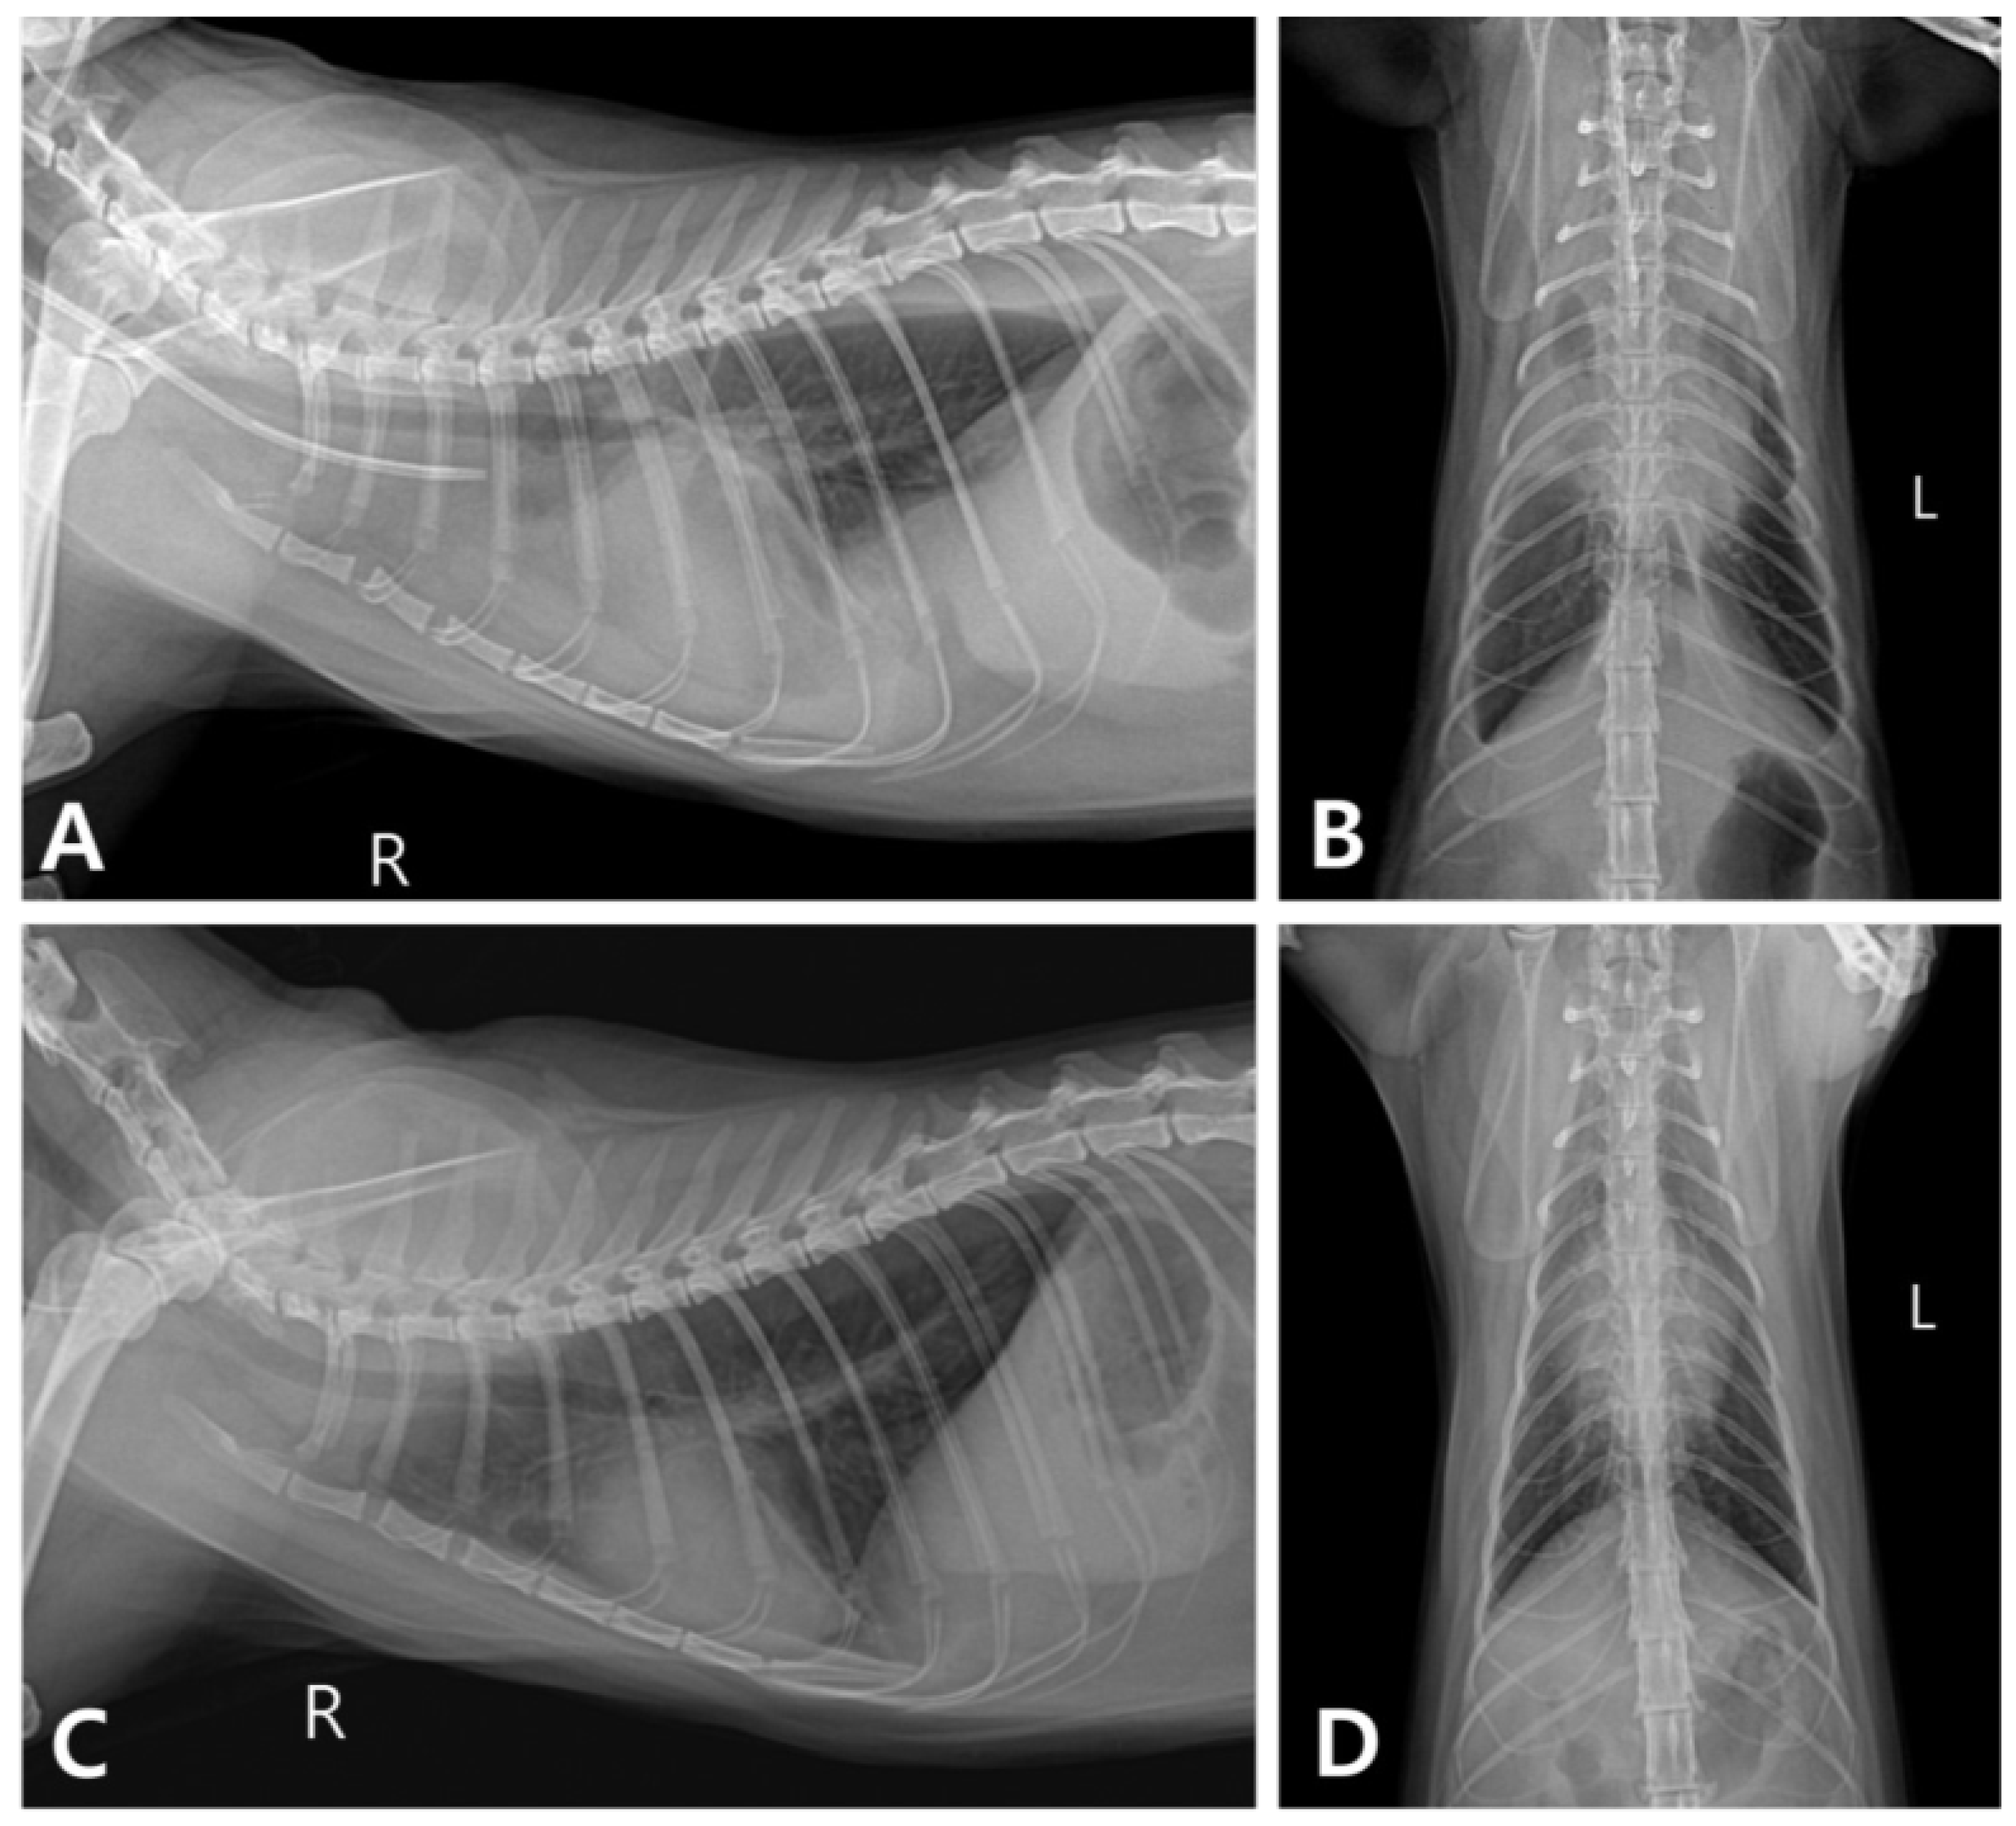

2. Case Description